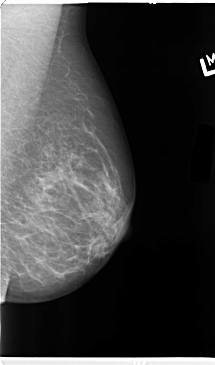

B_3101_1.LEFT_CC

LEFT_CC LINES 4632 PIXELS_PER_LINE 2632 BITS_PER_PIXEL 12 RESOLUTION 50 NON_OVERLAY